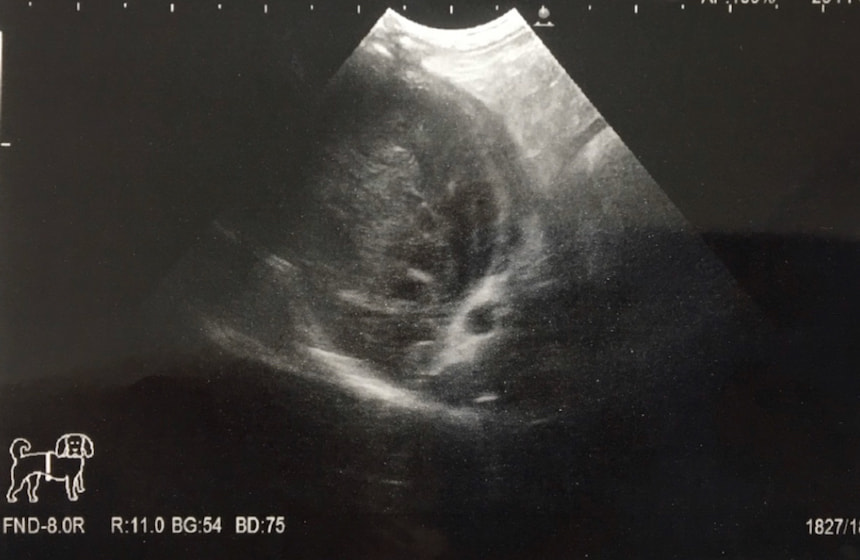

■ 症例 雑種猫 1歳 去勢雄

トイレにいる時間が長く、1回の排尿量が少ないとの主訴で来院。エコー検査にて、膀胱内に多量の微細砂粒を認めました。また、カテーテルが尿道の途中から入っていかず、砂粒が原因による尿道閉塞を起こしていることが確認されました。カテーテルから生理食塩水を注入することにより、詰まった砂粒を膀胱内に押し戻し、一時的に尿道閉塞を解除、尿検査の結果、微細砂粒はストルバイトと診断しました。食事療法および膀胱炎に対する対症療法を開始しましたが、連日尿道閉塞を繰り返すことから、会陰尿道瘻術を実施しました。術後は尿道閉塞の再発は無く、食事療法の継続で経過は順調です。